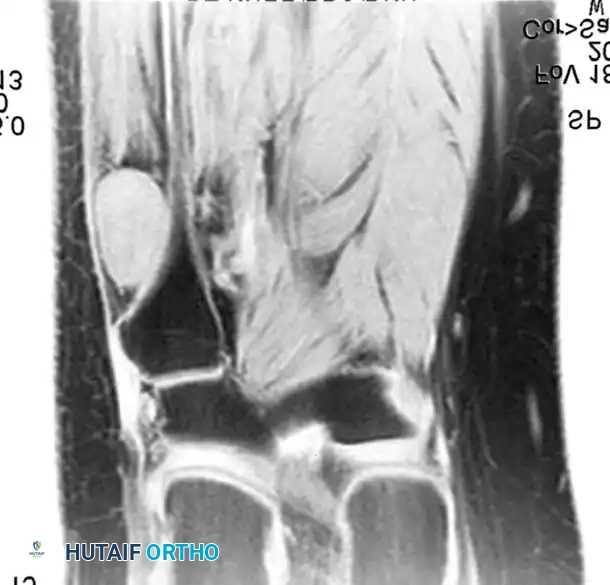

BENIGN TUMORS AND TUMOR-LIKE LESIONS Surgical Diagram

Axial and coronal MRI images showing a massive neurofibroma along the sciatic nerve in a patient with NF1.